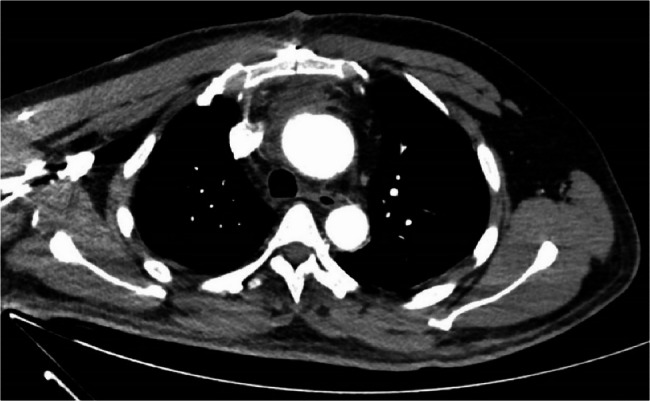

Methods: A 46-year-old male presented to a rehabilitation center with migrating right shoulder pain and proximal weakness. Initial complaint suggested a musculoskeletal disorder; however, further evaluation revealed hypertension, tachycardia, and migratory, intensifying pain. A subsequent computed tomography angiography confirmed AAD. The patient underwent urgent Sun's procedure, including ascending aorta and total arch replacement with stented elephant trunk implantation, which was followed by multidisciplinary rehabilitation due to the secondary ischemic stroke.